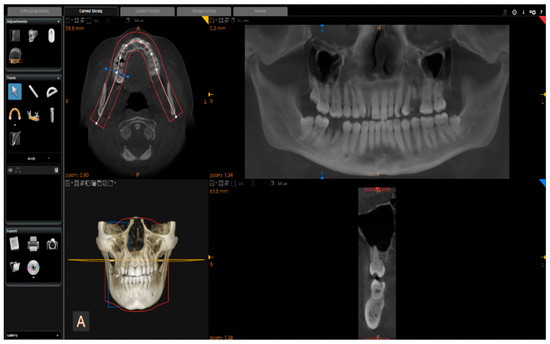

Images were reconstructed in C.S. 3D Imaging Software (Carestream Dent L.L.C., Atlanta, GA, USA). The head positions were standardized anteroposteriorly and sagittally according to a standard method. From CBCT volumes, the panoramic images were reconstructed by selecting a custom focal trough that passed through the lingual cusps of the maxillary teeth and extended posteriorly to the condyles. (Figure 2).

Figure 2. Reconstruction of panoramic images from CBCT volumes.